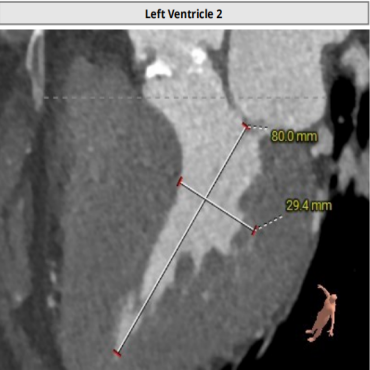

冠脉阻挡风险、左室大小及横位心评估

● 左室腔内径偏小、心室壁增厚,术前适当补液,术中密切关注血流动力学变化,预防循环崩溃。

为确保整个TAVR手术的安全性和有效性,宜昌市第二人民医院王庆海院长团队术前对患者病情进行的详细讨论,通过对主动脉根部CTA分析,明确本例患者具有二叶瓣椭圆形瓣环、瓣膜钙化程度重且不对称、瓣叶不等大、合并升主动脉扩张和近横位心、小左心室等独特的解剖特点;更重要的是,该患者存在瓣环-瓣叶开口大小不对等,若根据瓣环大小选择球囊会造成人工瓣膜支架展开不佳,置入位置偏深,从而导致瓣膜耐久性降低,残余瓣周漏,瓣环及周围结构破裂等严重手术相关并发症。因此此患者选择downsize、高位释放的策略,以达到更好的封堵效果。并且在术前进行适当补液,以预防术中循环崩溃风险。手中过程中王庆海院长团队选用二代可回收TaurusElite瓣膜,其采用高密度流入端和瓣膜内外双裙边设计,提供了足够的径向支撑力以应对高钙化的根部结构,同时保证了瓣膜的锚定力,内外双裙边可加速人工瓣膜内皮化,可进一步减少瓣周漏。本例患者瓣膜植入后瓣膜形态、位置良好,冠脉血流灌注正常,术后平均压差降至18mmHg,轻-中度瓣周漏,手术效果优异。TAVR手术是对医院整体实力、团队配合和个人综合技术水平的一场考验。高难度TAVR手术的成功实施,标志宜昌市第二人民医院治疗复杂主动脉瓣疾病的技术水平迈向了新的台阶,为饱受主动脉瓣疾病困扰的患者带去微创治疗的希望。